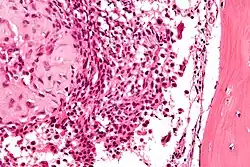

| Micrograph of a chondroblastoma. H&E stain. | |

Histological findings

Chondroid differentiation is a common feature of chondroblastoma.[1][4][6] A typical histological appearance consists of a combination of oval mononuclear and multi-nucleated osteoclast-type giant cells.[1][3][4] However this is not a prerequisite for diagnosis, as cells with epithelioid characteristics have been observed in lesions of the skull and facial bones.[4] A "chicken-wire" appearance is characteristic of chondroblastoma cells and is the result of dystrophic calcification that may surround individual cells.[1][5] Although, calcification may not be present and is not a prerequisite for diagnosis.[1][3][4] Mitotic figures can be observed in chondroblastoma tissue but are not considered atypical in nature, and therefore, should not be viewed as a sign of a more serious pathology.[1][4] There is no correlation between mitotic activity and location of the lesion.[4] Furthermore, the presence of atypical cells is rare and is not associated with malignant chondroblastoma.[1][6]